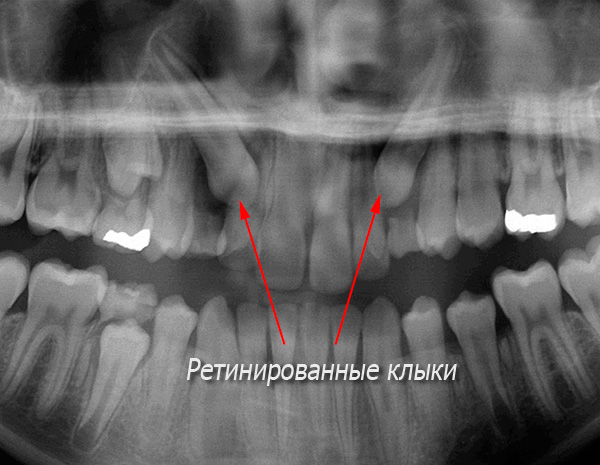

Non solo i denti del giudizio possono essere retinizzati. Ad esempio, "zanne superiori" e "premolari inferiori" (piccoli molari) possono "sedersi" nelle ossa o nelle gengive. Ma comunque, sono gli ottavi denti che si rivelano il più delle volte retinati.